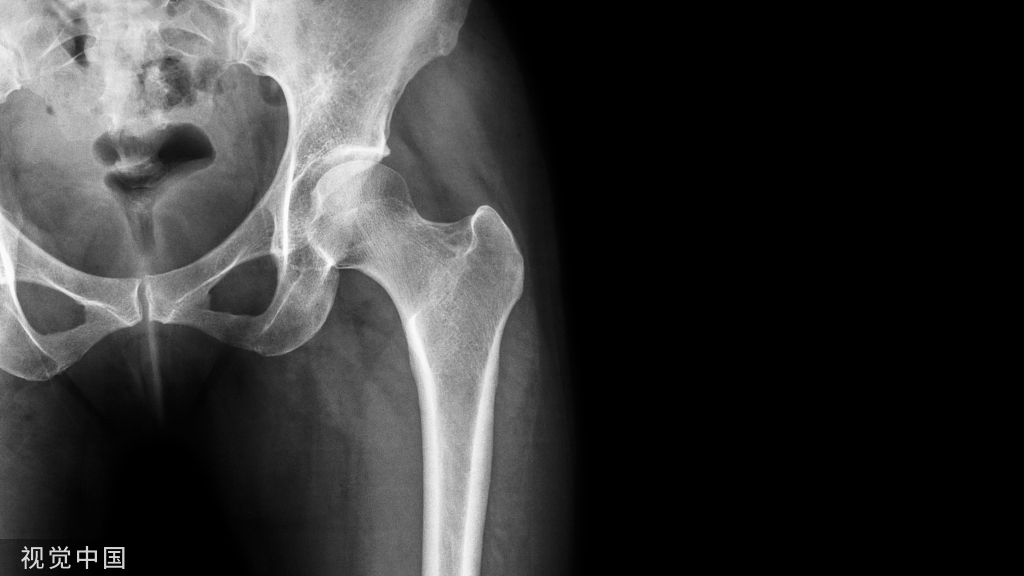

一.髋关节置换术

髋关节置换术是一种使用假体替换骨关节的治疗方式,主要涉及的部位是股骨部分、髋臼部分,通过骨水泥、螺钉等固定在患者的骨质上,取代其病变部位,从而重建髋关节的功能。

股骨头坏死、骨性关节炎、创伤性关节炎均能通过髋关节置换术治疗,常见的髋关节置换术中人工关节假体所用的材料以前多用不锈钢,目前绝大部分都是医用钛合金和陶瓷组合,但部分患者术后会发生严重疼痛及假体松动问题。